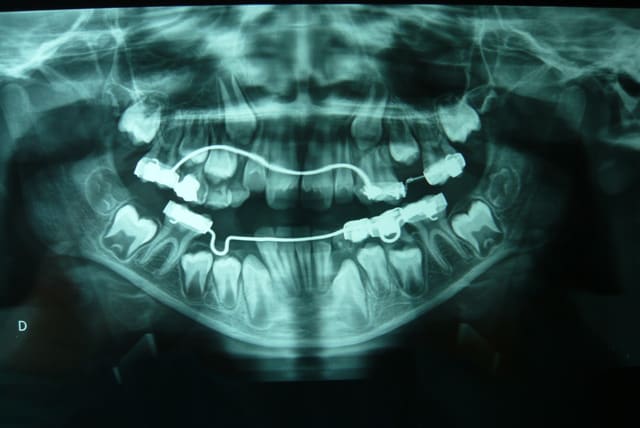

Sur un couloir de 17 mm, 3 germes se bousculant , décision d'extraction de la 44 (ODF).

Patient asa 1, 9ans.

Le manque d'espace relatif actuel est dû à la mésioversion de 46. La petite boucle du mainteneur n'est pas suffisante pour corriger cette version.

17mm, pour mettre 3 dents de 7mm, soit 21 mm. Déficit de 4 mm : Un D-gainer ( collage incisif avec ressort niti faible pour recréer de l'espace en étant legerement plus actif que la croissance naturelle).Ne pas oublier que c'est des germes de dents adultes, dans une mâchoire d'enfant, l'encombrement est quasi normal. Mais c'est trop tard..

Maintenant, on s'achemine vers germectomie de 34 14 et 24..

L'indication odf des extractions étant posé par un service CHU d'odf et doublement vérifié : en effet extract des 14/24/34/44

-cone beam réalisé avant l'acte permettant de visualiser le foramen situé ici entre germe de 4 et 5 donc inévitable lors de la chirurgie.